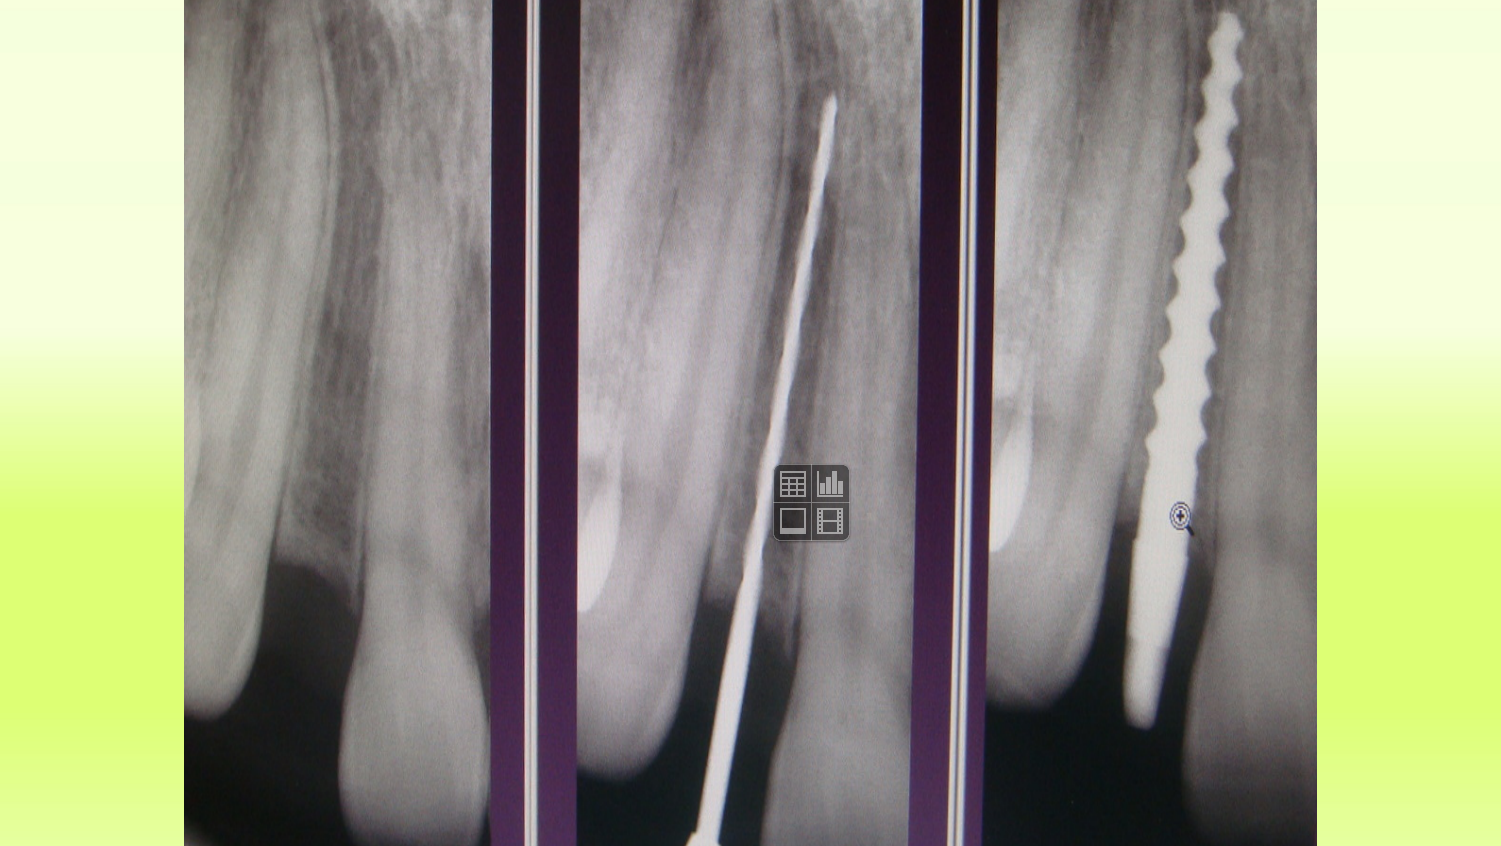

Case 12

“Vector” Implant placement in the area of 22 and 12 missing teeth is the only correct solution.